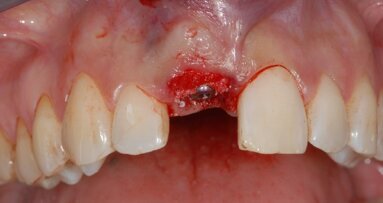

È stato inserito un impianto Straumann BLX 3.75 mm di diametro per 12 mm di lunghezza, con superficie SLActive seguendo l’asse protesico ideale (Figg. 4, 5). Avendo conseguito una stabilità primaria eccedente i 35 N/cm è stato realizzato un restauro provvisorio avvitato in composito su componente in Titanio da provvisori. Nonostante una sostanziale congruità della forma del provvisorio con la parte superficiale dell’alveolo, è stata utilizzata una matrice dermica suina (Botiss Mucoderm) allo scopo di sigillare il gap presente tra provvisorio e bordo mucoso dell’alveolo. Tale matrice, opportunamente sagomata e forata in modo da essere stabilizzata dal provvisorio stesso, è stata posizionata in modo da non rimanere esposta al cavo orale. Non sono state necessarie suture (Figg. 6-8).

Fig. 5_Rx periapicale post-impianto.